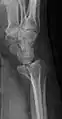

Radiografia projecional da fratura de Barton.

A fratura de Barton é a fratura óssea intra-articular do rádio distal, com deslocamento da articulação radiocarpal.

Há dois tipos de fratura de Barton – a dorsal[1] e a palmar, sendo a última mais comum. A fratura de Barton é causada pela queda sobre um pulso pronado, causando o aumento da compressão carpal na sua borda dorsal. O componente intra-articular distingue esta fratura da fratura de Smith e da fratura de Colles. O tratamento dessa fratura em geral é feito por redução aberta e fixação interna com placa e parafusos, embora ocasionalmente a fratura desse tipo seja tratada de forma conservadora - isto é, com gesso.